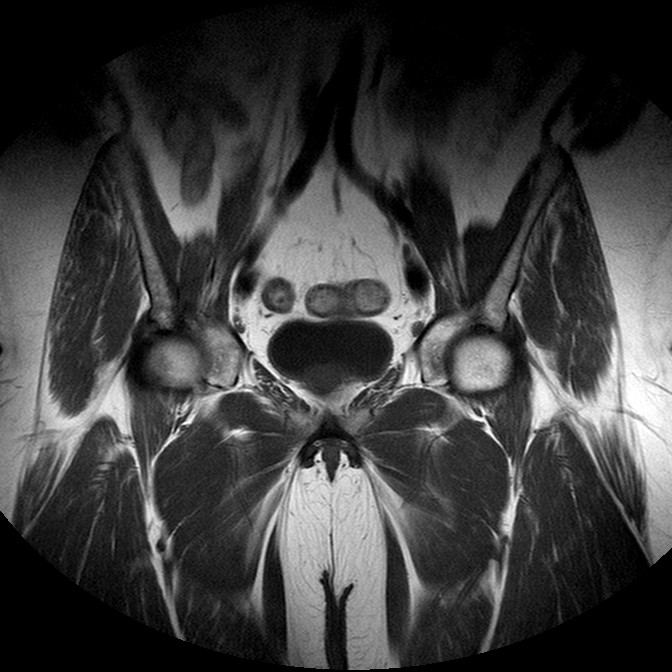

Esami: RMN BACINO

T1w TSE

Evidenti e simmetriche alterazioni osteofitosiche in regione coxo femorale con riduzione delle rime articolari. Degenerazione completa del cercine glenoideo. Non attuali segni di versamento articolare. Non segni di edema osseo che escludono attuale algodistrofia od osteonecrosi. Lieve e simmetrica riduzione del trofismo della muscolatura glutea.